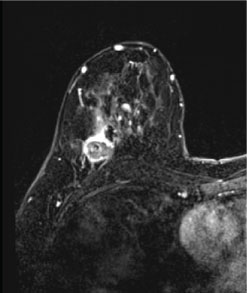

Ultrasound has a very high sensitivity for the detection of TNBC [3]. The most frequent presentation of TNBC on ultrasound is as a discrete mass which, as on mammography, largely lacks suspicious sonographic features (Figure 2). The predominant features of TNBC include well-circumscribed margins, reported in approximately 25% of cases [3,11-13], and posterior acoustic enhancement, present in 25-40% of cases [3,12,13]. The presence of posterior acoustic enhancement in TNBC suggests tumor necrosis, rather than indicating benignity as in other breast lesions [3,14,15].

Figure 2: Ultrasound findings in triple-negative breast cancer (TNBC). Right breast ultrasound demonstrates an oval, hypoechoic mass with circumscribed margins and associated posterior acoustic enhancement, representing a biopsy-proven TNBC. View Figure 2